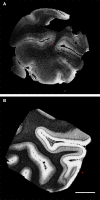

Ex vivo magnetic resonance imaging yields high resolution images that reveal detailed cerebral anatomy and explicit cytoarchitecture in the cerebral cortex, subcortical structures, and white matter in the human brain. Our data illustrate neuroanatomical correlates of limbic circuitry with high resolution images at high field. In this report, we have studied ex vivo medial temporal lobe samples in high resolution structural MRI and high resolution diffusion MRI. Structural and diffusion MRIs were registered to each other and to histological sections stained for myelin for validation of the perforant pathway. We demonstrate probability maps and fiber tracking from diffusion tensor data that allows the direct visualization of the perforant pathway. Although it is not possible to validate the DTI data with invasive measures, results described here provide an additional line of evidence of the perforant pathway trajectory in the human brain and that the perforant pathway may cross the hippocampal sulcus.